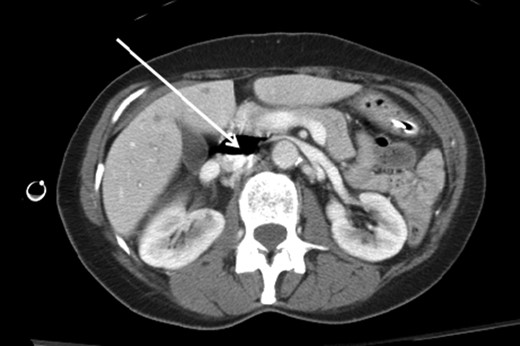

A 66-year-old female patient presented to our level I trauma center after a motor vehicle collision. She sustained multiple injuries including several fractured ribs, hemopneumothorax and a right diaphragmatic rupture. She was hemodynamically normal during her primary and secondary survey, and received a right femoral vein central venous catheter (CVC) for fluid resuscitation. She underwent computed tomography (CT) scan for further diagnostic evaluation and was noted to have the aforementioned injuries and a significant amount of air within the IVC, right iliac and femoral veins (Figs. 1–3). She was immediately placed in Trendelenburg position; a new subclavian CVC was inserted and used to withdraw air. Her right femoral vein introducer was suspected to be the source and was removed. She remained stable with no obvious clinical sequelae and underwent operative repair of her diaphragmatic injury. The patient was discharged on hospital Day 10 with no issues.

Axial CT image of the pelvis demonstrating the CVC (white arrow) with adjacent air (red arrow) in the right external iliac vein.